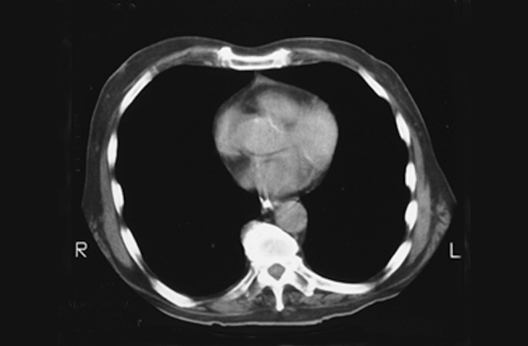

Heart CT

1. Right atrium

2. Right ventricle

3. Left ventricle

4. Left atrium

5. Descending aorta